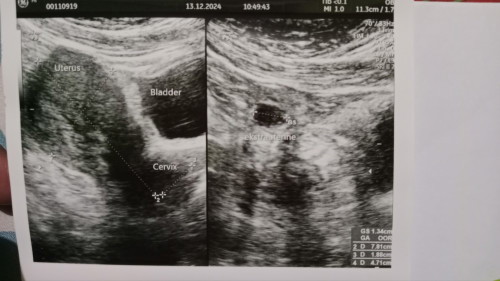

Usia kehamilan dihitung dari hpht 8week, dinyatakan kehamilan ektopik

#Sharing_dong_Bund ada yang sama ga bun.. Se pengalaman sama q.. Pas USG pertama q lgsung k dokter obgyn dan dinyatakan positif hamil namun baru penebalan dinding rahim bahkan sudah USG transvaginal pun hasil nya sama. Dan hari ini q USG lg k dokter obgyn yg berbeda bun, namun dinyatakan terjadi kehamilan ektopik. Udh gk karuan bgt fkiran q bunda... q periksa krna ada flek kecoklatan tanpa ada y rasa sakit perut/kram/mules.. Makanya lgsung q USG brusan bun, kantung kehamilan nya sudah terlihat skrg namun malah dinyatakan q hamil dluar kandungan.. Bunda bunda minta solusinya dong q hrs gmn ya, pa bnr hrs tindak oprasi ke RS besar bund.. Apa msh ada harapan untuk mnggu keajaiban bhwa smua y akan baik2 aja, udh stresss bgt q bund nangis trs ini 😭😭😭😭#bantujawab